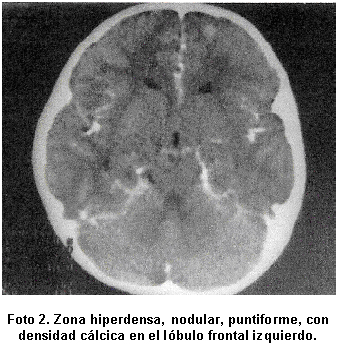

En el Cuadro 3 se describen las lesiones parasitarias halladas en los estudios de neuroimagen, que se localizaron en el lóbulo frontal (Foto 1) y (Foto 2). La TAC evidenció lesiones en cuatro pacientes y sólo en un caso se requirió la RMN para detectar lesión estructural (Foto 3). La tomografía de control reveló lesiones calcificadas en 4 pacientes (80%) y resultó normal en un caso. El estudio electroencefalográfico mostró ondas lentas focales de localización temporo-occipital bilateral en una paciente. La prueba de ELISA fue negativa en todos los casos.